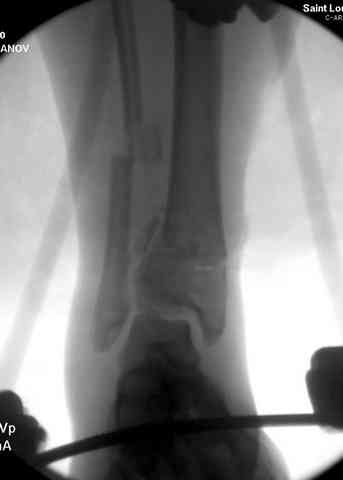

Дополнительные ренгенограммы после дистракции и

обязательная комьютерная томография дают возможности разузнать топографию расположения фрагментов, что немаловажно для планирования хирургического доступа.

По апексу фрагмента ориентируется при планировании

фиксации, также предоперационно определяется

направление фиксирующего материала: шурупа или спицы с упорной площадкой.

Здесь выставлена пара случаев перелома пилона, оба

случая леченные этапным наружным фиксатором.